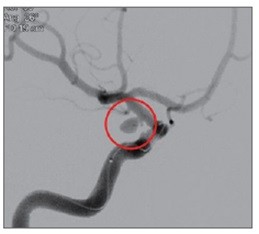

뇌동맥류를 파열 전 발견해 치료하면 95% 이상에서 좋은 결과가 나타난다. 치료는 주로 ‘클립결찰술’과 코일색전술’로 이뤄진다. 클립결찰술은 이마 부위 두개골을 열고 클립 같은 고정 핀으로 부풀어 오른 뇌동맥류를 졸라매는 수술법이다. 코일색전술은 머리를 절개하지 않고 사타구니에 있는 대퇴동맥을 통해 뇌동맥에 가느다란 도관을 넣은 뒤 뇌동맥류 내부를 백금 등으로 만들어진 특수 코일로 채워 막는 방식이다. 뇌수술이 어렵거나 직접수술이 위험성이 큰 환자에게 적합하다.